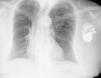

A 74-year-old woman had undergone implantation of a permanent pacemaker (VDD) for grade 3 atrioventricular block two years previously, with no intervening complications. At a routine follow-up consultation, although she presented no symptoms, pacemaker dysfunction was detected (undersensing and failure to capture). A posteroanterior chest X-ray showed the pacemaker lead tip protruding outside the heart (Figure 1). Thoracic 16-slice multidetector computed tomography, with multiplanar and three-dimensional reconstructions, confirmed the position of the lead tip outside the heart, with an intrathoracic course towards the diaphragm (Figures 2–4).

Most patients with myocardial perforation are symptomatic, with chest pain, dyspnea, hypotension or pacemaker dysfunction. Occasionally there may be symptoms triggered by stimulation of the chest wall muscles or hiccups through stimulation of the diaphragm. More rarely, as in the present case, the patient can be completely asymptomatic, and a high level of suspicion is required. Conventional X-ray and computed tomography can confirm the diagnosis and determine the lead course.